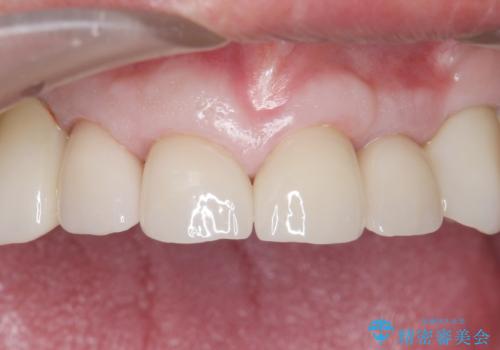

審美的な仕上がりと自然な咬み心地に喜んで頂けました。

治療前は口元を隠すようにお話しされていたのですが、治療後はそれもなくなり、満面の笑顔を見せて下さいました。

クラウンの種類:オールセラミッククラウン スタンダード